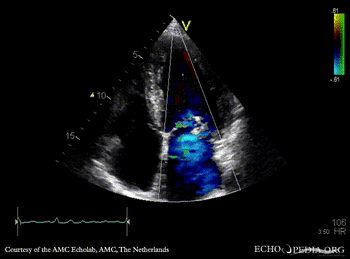

| A2CH | PLAX: Color Doppler, severe mitral regurgitation, excentric jet |

| A4CH: Color Doppler, severe mitral regurgitation, excentric jet | |